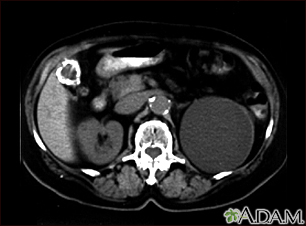

Kidney cyst with gallstones - CT scan